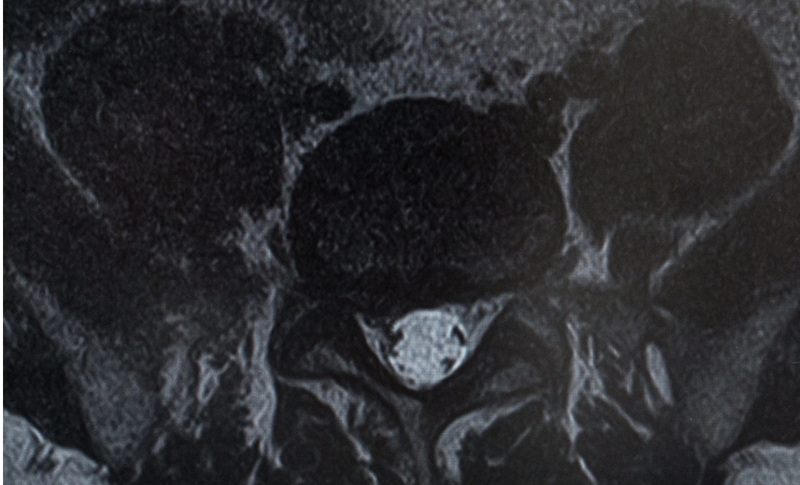

頚椎ヘルニアは、首の骨の頚椎と呼ばれている部分の椎間板が飛び出している状態です。

椎間板がダメージを受けて、飛び出していると、神経を圧迫して様々な症状をおこしてしまいます。